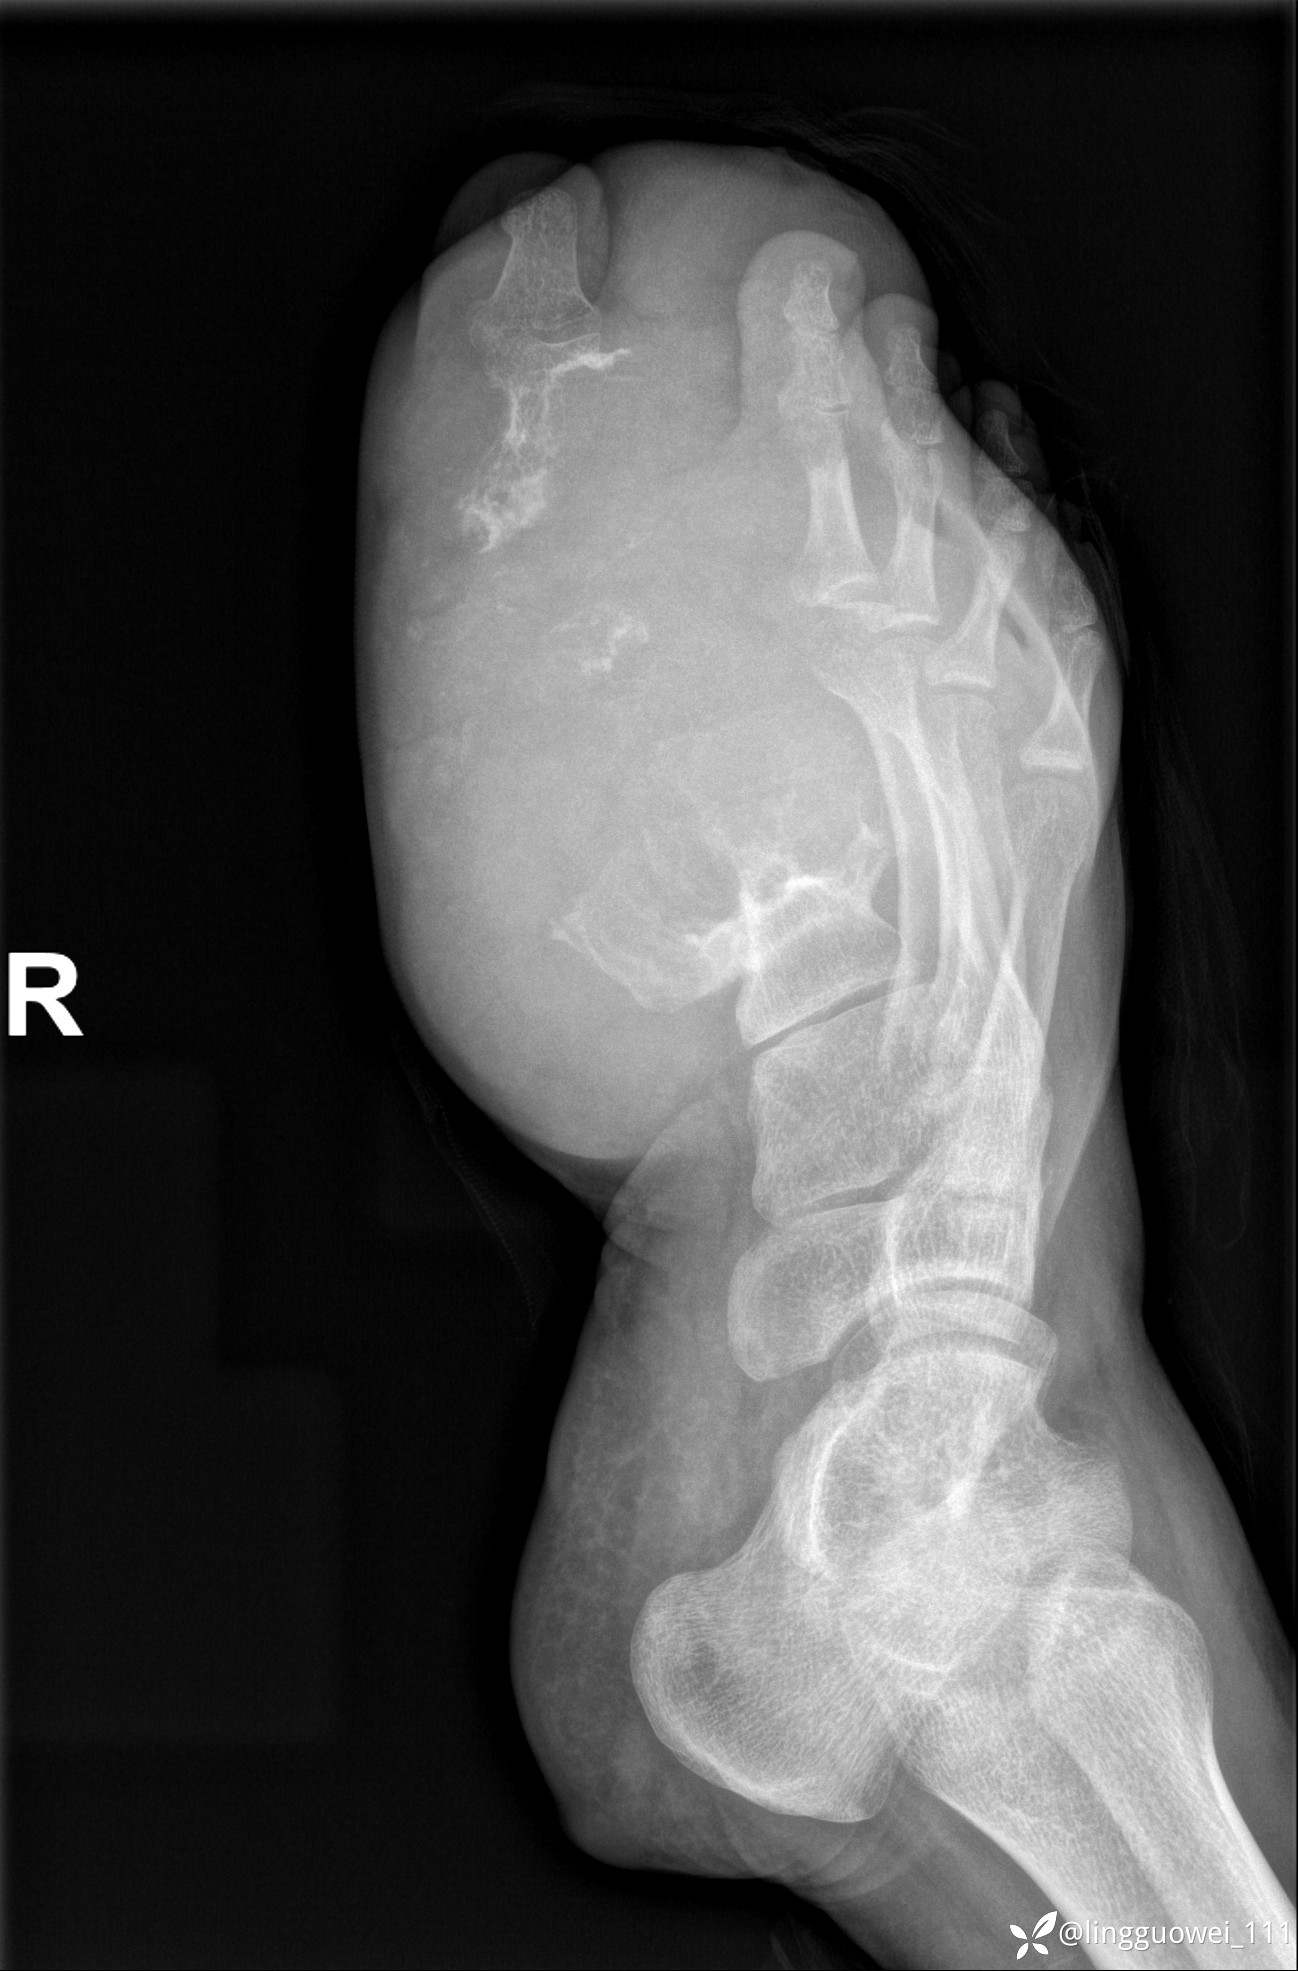

28岁男性,工作中遇到的足部最大的肿块,已补充临床资料。

28岁男性,足部肿块逐渐增大2年。能找到病因吗?

患者于2年余前高嘌呤饮食及大量饮酒后出现全身多处关节痛风石,以右足第一跖趾关节和右手为显,局部红肿热痛反复发作,自行口服药物后可缓解(药物可疑为强的松、双氯芬酸钠等,具体不详)。2年来右足痛风石明显增大,约10cm*5cm*15cm,局部红肿发热,3天前患者再次大量饮酒后痛风石顶部破溃,可见4cm*3cm皮损,较多白色豆渣样分泌物流出,为求进一步治疗来诊,门诊诊断为“右足痛风石破溃伴感染”, 收住院拟手术治疗,患者起病以来,无发热,精神佳、胃纳好、睡眠佳,大小便正常。

专科检查:右足外观畸形,足背部可见巨大痛风石形成,痛风石大小约10cm*5cm*15cm,局部皮肤红肿发热,痛风石顶部破溃,可见4cm*3cm皮损及白色豆渣样分泌物流出;痛风石界限清,质偏硬,局部触及波动感,无压痛,移动度差。右足踇趾及第2趾被痛风石压迫,关节活动受限。肢端血运、感觉无异常。 右手稍肿胀,2-5指背侧可见多发痛风石形成,最大者约花生米大小,皮肤完整未破溃,痛风石界限清,质偏硬,局部触及波动感,无压痛,移动度差。